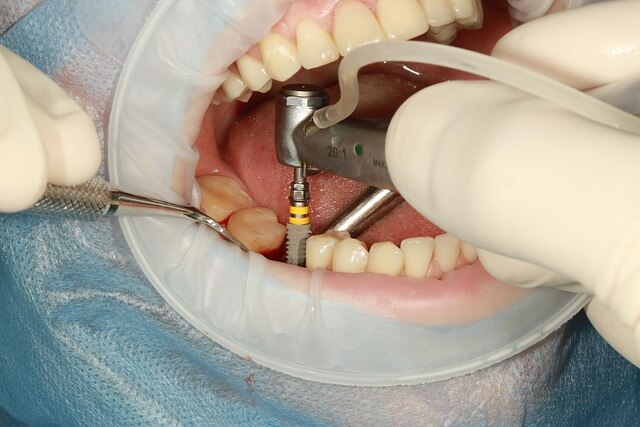

*임플란트 시술과정 시술순서에서 중요한 포인트는 검사가 끝난 뒤 바로 1차 수*이 시작된다는 점입니다. 이 단계에서 인공 뿌리를 잇몸 뼈에 심는데, 마취하니 통증 걱정은 덜 하셔도 됩니다. *이 과정이 제대로 돼야 다음 단계가 원활하게 이어지니 꼭 믿고 맡기셔야 해요.

*골유착이 마무리되면 2차 수*이 진행돼 임플란트에 지대주라는 작은 기둥을 연결합니다. 이 단계는 임플란트 시술과정 시술순서에서 꽤나 중요한 부분인데, 지대주가 있어야 나중에 인공 치아를 단단히 붙일 수 있거든요. *많은 분들이 두려워하지만 절개 후 빨리 회복되는 편이라 걱정은 덜어도 됩니다.